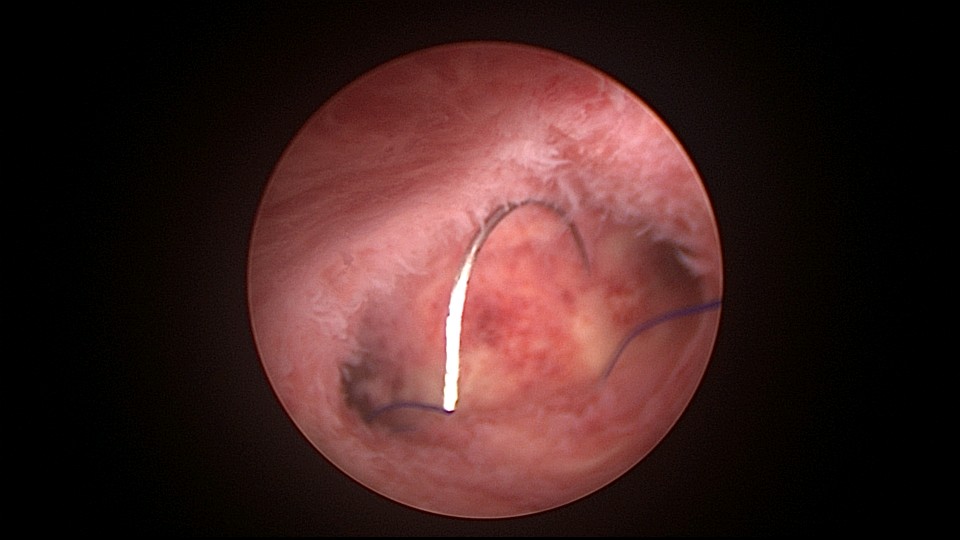

患者38岁,G5P1,剖宫产1次。2023年1月节育环下移带环受孕,宫腔镜取环终止妊娠,同时行左手上臂内侧皮埋避孕,遗憾的是手术医生术中没有找到节育环,术毕复查B超,环仍在宫腔,第二天宫腔镜探查,节育环位于切口憩室内,取出节育环。再次遗憾的是取环后阴道淋漓不净出血,术后第24天复查B超见胚物残留,第三次宫腔镜手术清除残留组织。2025年10月取出皮埋棒,2025年11月外院安环,术后2周复查B超环下移,2025年12月(月经干净3天后),安环医院取出节育环,取环后第6天到我院行宫腔镜安环并做节育环固定。子宫水平位,宫深8.5cm,见切口憩室比宫腔更宽大,形成类似金字塔形状(2次节育环下移原因),行宫腔镜下缝合线结固定节育环,打了3个结,拉过缝合点2个结。第十七例节育环固定。既往带环受孕,多次宫腔镜手术。术后2周复查B超,节育环位置正常,环顶端距宫底1.6cm。